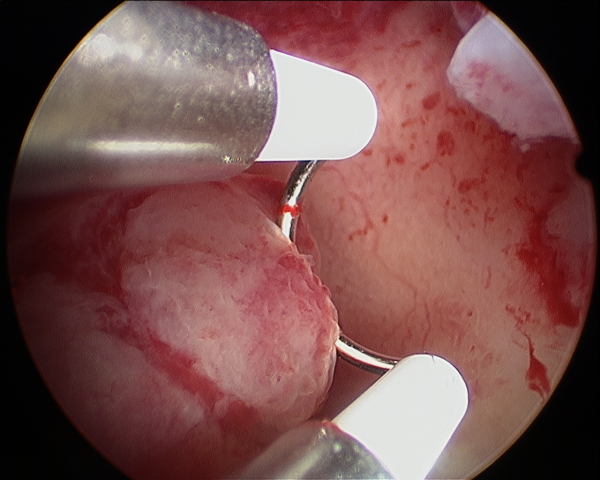

3)Histeroskopik sineşi açılması veya adezyolizis

Geçirilmiş myom ameliyatı, doğum sonrası kürtaj veya sezaryen gibi ameliyatlardan sonra ve rahim tüberkülozundan sonra rahim iç tabakasında yapışıklıklar oluşabilir. Bu hastalarda adet hiç olmayabilir, adet kanaması normalden az olabilir. Adet döneminde şiddetli ağrı olabilir. Yapışıklık çok az olsa bile hastalar gebe kalamayabilir veya düşük olabilir. Çocuk sahibi olmak isteyen hastalarda tedavi histeroskopi ile yapışıklıkların açılmasıdır.